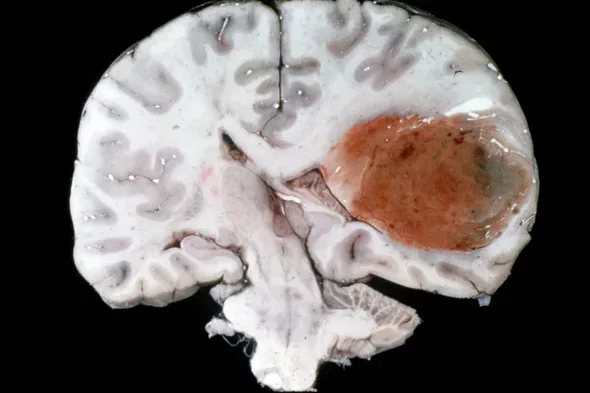

We study immune-based therapies for the treatment of central nervous system (CNS) tumors

Despite recent advances in traditional treatment options, the prognosis for most CNS tumor patients has not changed appreciably in twenty years. Thus, these patients are left with few treatment options. Members of our research group are attempting to apply what they learn from pre-clinical models towards the implementation of immunotherapy clinical trials for brain tumor patients. This work is translational in nature and straddles the boundary between clinical medicine and basic research. On one hand, our group spends a significant amount of time trying to understand the mechanisms by which tumor-specific T-cells can be activated to target tumor cells in the brain. On the other hand, Dr. Prins leads the laboratory effort for immunotherapy clinical trials at UCLA in glioma patients. This work represents the “bench to bedside” philosophy and is an active synergy between laboratory and clinical medicine.